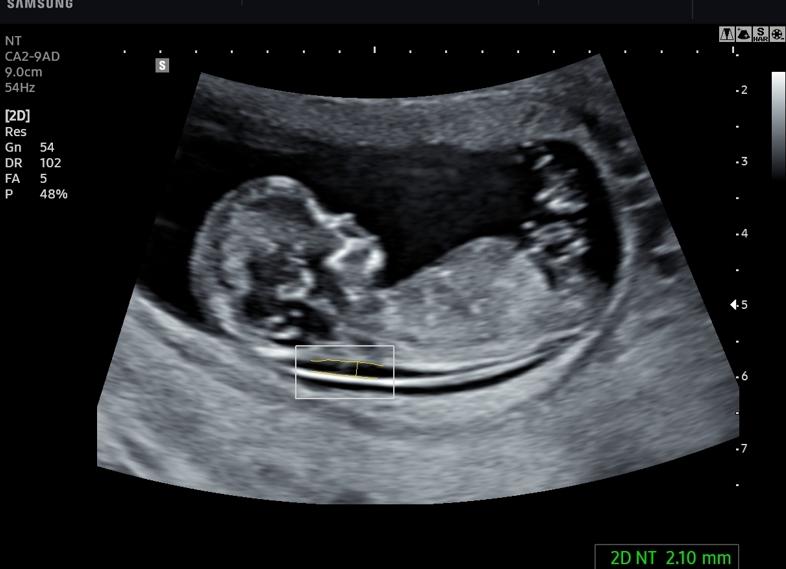

• толщину воротниковой зоны (в среднем, на 10 неделе норма – 2 см, не больше),

Толщина воротникового пространства (ТВП)

11 недель — 0.8-2.2 мм

12 недель — 0.8-2.5 мм

13 недель — 0.8-2.7 мм

При помощи УЗИ определяют телосложение будущего ребенка, все ли у него «на месте», правильно ли расположены ручки и ножки. Кроме того, делают специальные измерения (вымеряют толщину шейной складки). Врач исследует кровоток у плода, работу сердца, соответствие длины тела срокам беременности. Также определяют толщину воротникового пространства у эмбриона. Если его величина отличается от нормы, то повышается риск возникновения генетических нарушений.

2. Толщина воротниковой зоны

Нормы УЗИ 1 триместра в отношении этого важнейшего маркера хромосомных патологий:

• в 10 недель – 1,5-2,2 мм

• скрининг 11 недель представлен нормой 1,6-2,4

• на 12 неделе этот показатель – 1,6-2,5 мм

• в 13 недель – 1,7-2,7 мм.

• Толщина воротникового пространства (ТВП). ТВП – это расстояние между мягкими тканями шеи и кожей. Увеличение толщины воротникового пространства может говорить не только об увеличении риска рождения ребенка с синдромом Дауна, но и о том, что возможны другие генетические патологии у плода.